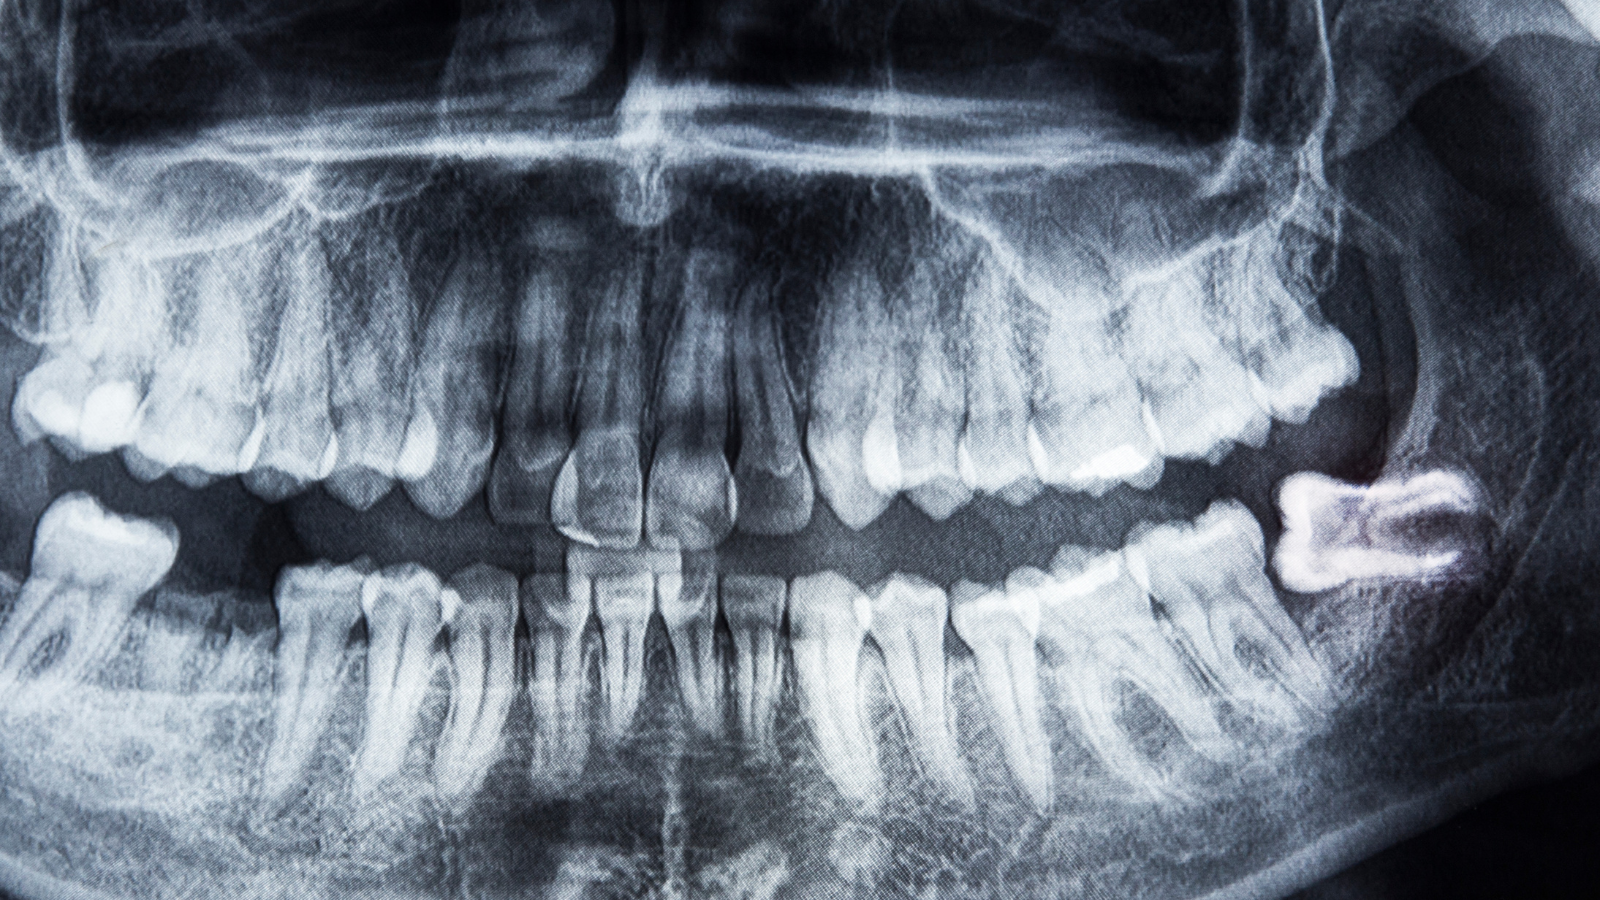

一般的な歯科医院では、初診時にパノラマレントゲン(お口全体を撮影する大きなレントゲン)や、デンタルレントゲン(歯を数本ずつ撮影する小さなレントゲン)を撮影します。

パノラマレントゲンは、上下の歯全体と顎の骨を一度に撮影できるレントゲンで、保険診療では約400点(約4,000円)、3割負担で約1,200円程度です。

虫歯の有無や親知らずの状態、顎関節の異常などを広範囲に確認できるため、初診時によく使用されます。

歯周病は、歯を支える骨が溶けていく病気で、進行すると歯が抜け落ちる原因となります。

骨の状態は目視では確認できないため、レントゲン撮影が必須となります。

歯周病検査では、歯と歯茎の間の溝(歯周ポケット)の深さを測定し、レントゲンで骨の減少具合を確認します。